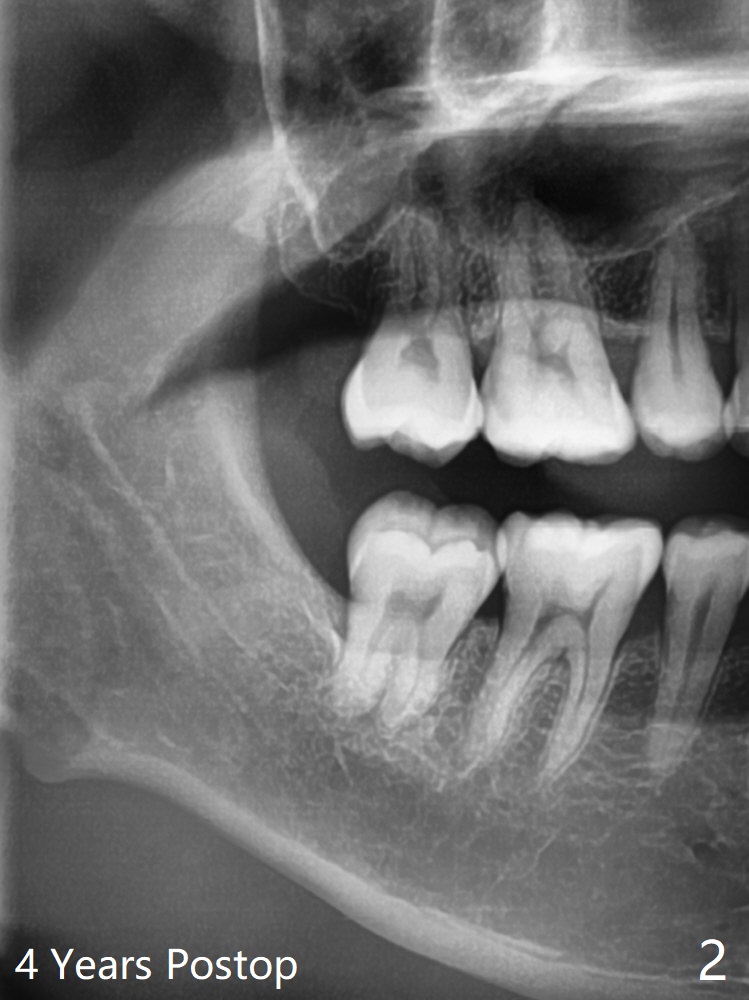

A 34-year-old man requests extraction of #1 and 32 (Fig.1). With placement of Osteogen Plug at #32 after extraction, the socket is filled with bone 4 years postop (Fig.2).